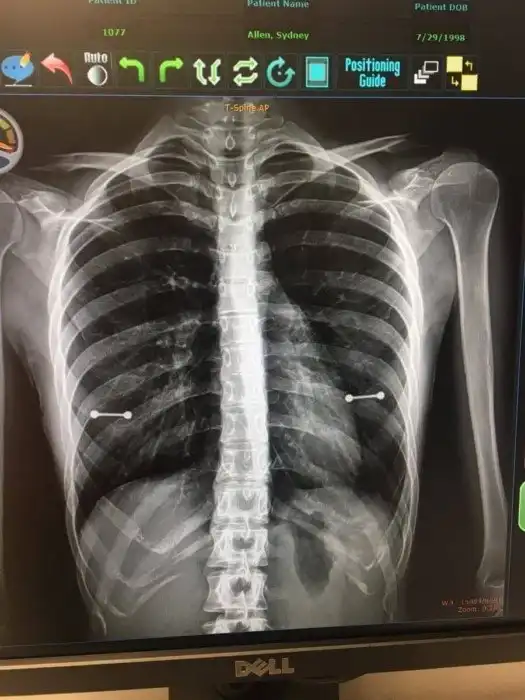

16. Американка сделала пирсинг и пыталась скрыть его от мамы. И ей бы это удалось, если бы не законы физики

Девушка по имени Сидни Аллен сделала пирсинг в секрете от мамы, но тайное стало явным во время визита к врачу.